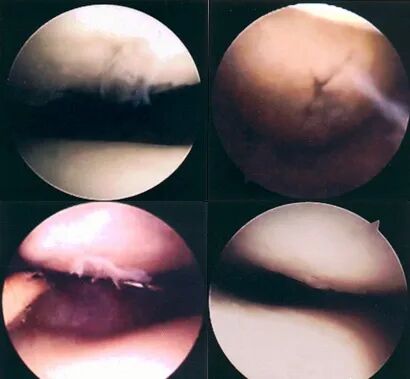

关节镜下可将髌骨软化分为5级:

0级:正常关节软骨

Ⅰ级:关节软骨失去珍珠样外观而变得较暗淡,局部软化,肿胀区或纤毛化区的直径<0.5cm。

Ⅱ级:关节软骨软化区内出现毛刷状或纤毛化改变,深达1~2mm,直径≤1.3cm。

Ⅲ级:软骨的毛刷状或纤毛化改变达关节软骨厚度一半以上,直径>1.3cm,关节软骨表面类似蟹肉样改变,表面有多发软骨碎片附着其下的软骨。

Ⅳ级:关节软骨全层受侵,软骨下骨暴露,表现为进展期髌股关节炎。

Ⅰ~Ⅱ级为早期,主要保守治疗。

Ⅲ~Ⅳ级为进展期,需手术及关节镜治疗。

• 关节镜:是髌骨软化症确诊与治疗的有效手段之一,可以在镜下直接观察软骨面的变化,但不能够观察到软骨下骨的变化